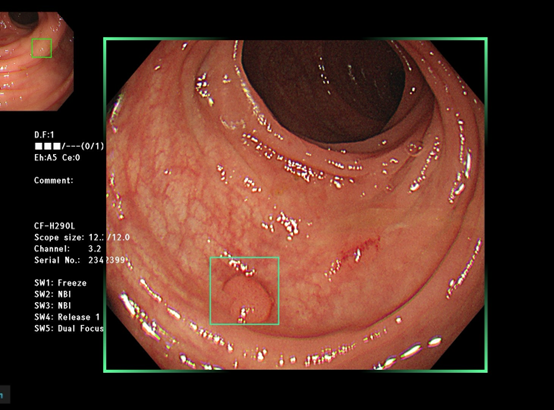

大腸鏡近年來整併了AI圖像辨識技術,可以第一時間透過電腦判讀,知道大腸癌的風險高低,大幅增加了大腸癌檢查的效率以及準確性。國外研究顯示施行大腸鏡時的腺瘤偵測率每提升1%,將可以降低鏡檢後發生大腸癌風險3% 之多,死亡率甚至可以降低5%。2022年國外研究顯示,藉AI人機協作進行大腸鏡檢查,約可提高14% ~ 30% 的腺瘤偵測率不等。

除了癌症判定,經由特殊光譜NBI、BLI以及放大效果,也可協助醫師立即 診斷瘜肉的好壞。簡單來說,就是讓 內視鏡 的訊號經過AI BOX即時處理,就能即時顯示於螢幕上,類似於醫師的第三隻眼睛,幫助揪出不易用肉眼檢視到的瘜肉。